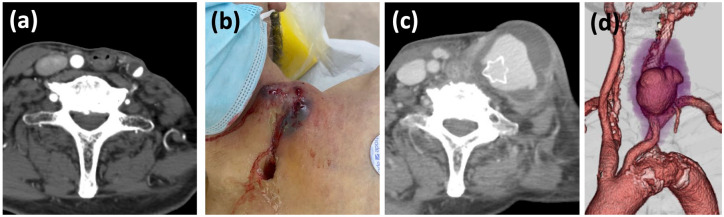

颈动脉爆裂综合征(CBS)是一种潜在的致命疾病,需要及时诊断和干预。CBS主要影响有头颈部恶性肿瘤手术或放疗史的患者。在本报告中,我们描述了一例CBS病例,该患者颈动脉支架植入术2个月后颈动脉破裂,既往有咽癌手术和放疗史。虽然颈总动脉口与破裂部位之间的距离很短,但“无接触”技术-在引导导管导航期间使用牛顿形硬内导管(Newton-T®,Medikit) -和圈套固定使手术稳定。两个自膨胀覆盖支架(GORE®VIABAHN®,GORE)覆盖破裂部位。尽管条件不利,但这些技术的结合导致了对即将发生的CBS(一种潜在的致命疾病)的有效管理。本病例报告强调了覆盖支架治疗CBS的可行性,以及在整个手术过程中用于引导导管导航和稳定的技术。

Carotid blowout syndrome (CBS) is a potentially fatal condition requiring prompt diagnosis and intervention. CBS primarily affects patients with a history of surgery or irradiation for head and neck malignancies. In this report, we describe a case of CBS in which the carotid artery ruptured 2 months after carotid artery stenting in a patient with a previous history of surgery and irradiation for pharyngeal cancer. Although the distance between the orifice of the common carotid artery and the ruptured site was short, the "no-touch" technique-using the Newton-shaped stiff inner catheter (Newton-T®, Medikit) during the guiding catheter navigation-and snare fixation enabled a stable procedure. Two self-expanding covered stents (GORE® VIABAHN®, Gore) covered the ruptured site. Despite adverse conditions, the combination of these techniques led to effective management of impending CBS, a potentially fatal disease. This case report highlights the feasibility of covered stents for CBS and the techniques used for guiding catheter navigation and stabilization throughout the procedure.